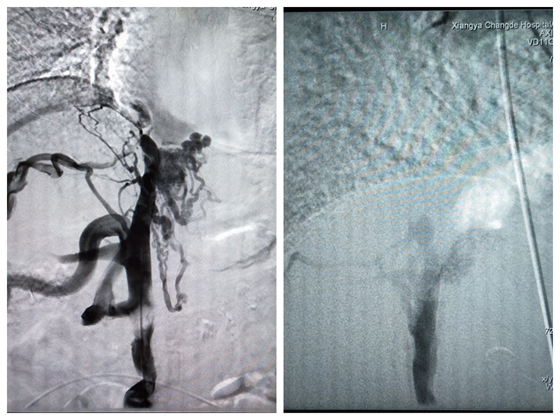

家住湖南南县的李阿姨,4月前曾因脑外伤在湘雅常德医院神经外科就诊,经历一番详细检查,医生却意外发现患者双下肢色素沉着,询问患者才知其症状已持续一年了。通过全方位检查,患者下腔静脉闭塞,肝静脉显影不佳,并腹腔内多发静脉迂曲增宽,腰静脉及腹壁静脉增宽,奇静脉开放,脾肾分流,考虑为布加综合征。

布加综合征术前

布加综合征是由于肝静脉和(或)下腔静脉血流受阻导致门静脉及下腔静脉高压的临床综合征。其临床表现多样,具有特征性短期内出现大量腹腔积液,肝脏增大,如果不及时诊断及治疗,将会导致门静脉高压及食管静脉曲张破裂出血、肝功能不良、凝血功能障碍,晚期更是会导致肝衰竭和肝性脑病致死。李阿姨则是因为此病引起的静脉性淤血而造成双下肢色素沉着,但当时李阿姨存在脑外伤,医生建议延期手术。